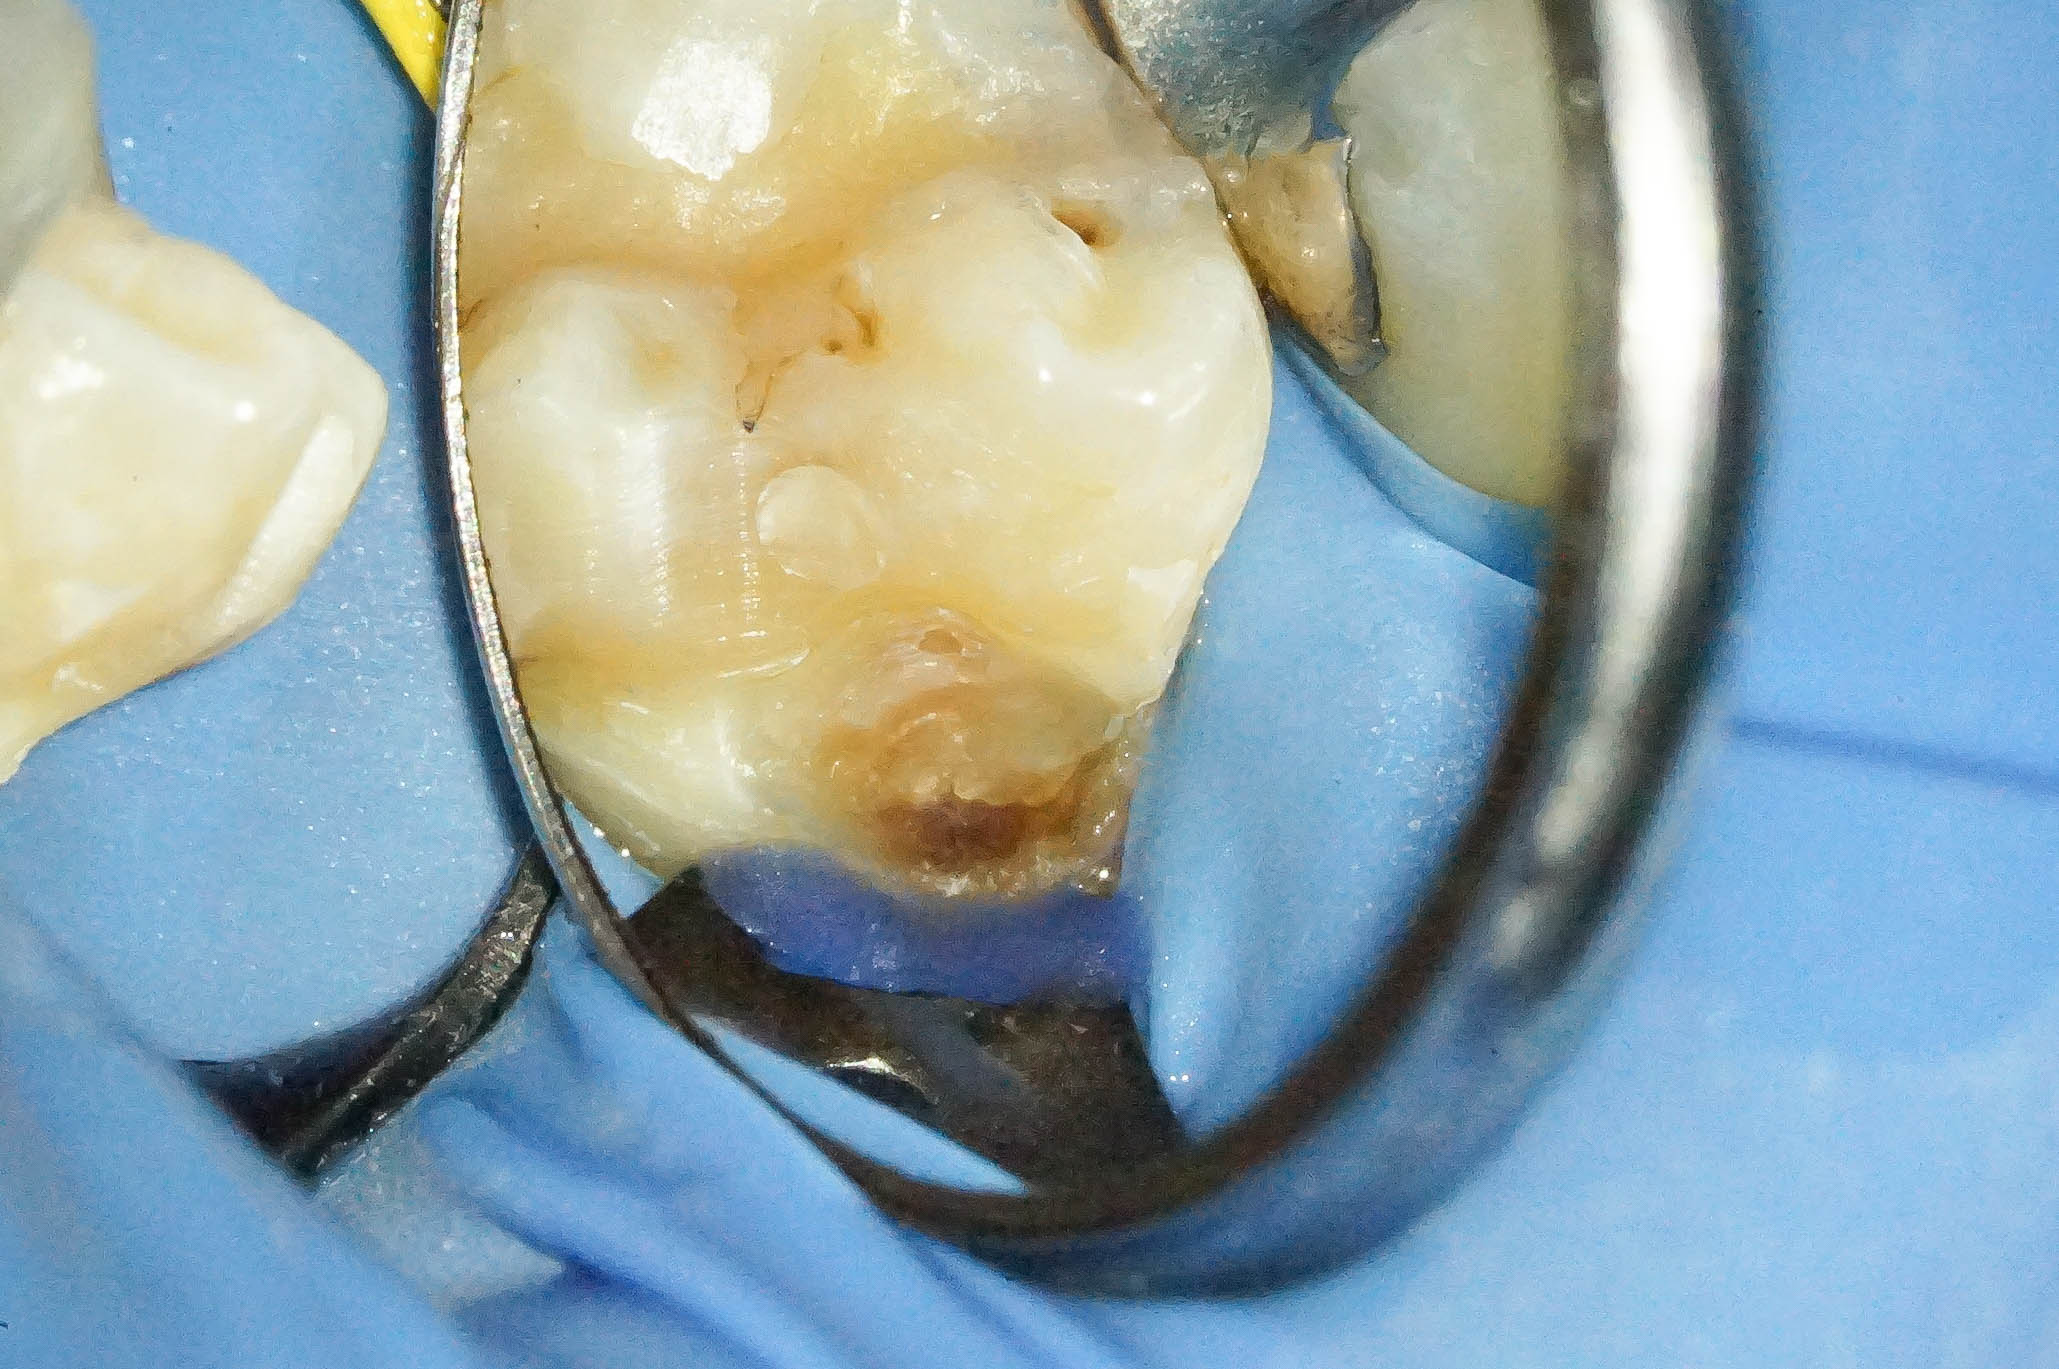

歯肉縁下ダイレクトボンディングを行った症例治療方法04

歯周外科を行うことでウ蝕部分をしっかりと明示できるので、ウ蝕の取り残しをなくすことができます。

そして難易度は高いですが、その部位にラバーダムを設置します。

ラバーダムがなければ処置部位は血まみれ、唾液まみれで繊細な治療ができません。

歯肉縁下ダイレクトボンディングを行った症例治療方法05

古いコンポジットレジンを除去したところ、やはり内部でウ蝕が広がっていました。

確実な視野の確保、そして清潔な領域を守りつつ作業ができるので、ラバーダムの効果は絶大です。